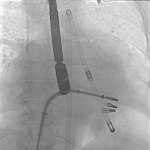

Zespół z Uniwersyteckiego Szpitala Klinicznego w Opolu użył pompę wspomagającą pracę serca, aby zmniejszyć rozmiary serca pacjenta, a następnie wykonać zabieg na zastawce mitralnej.

- Zastawka mitralna u pacjenta była tak poszerzona, że przezskórny zabieg naprawczy nie był możliwy - wyjaśnia kierujący zespołem kardiolog dr hab. n. med. Jerzy Sacha, kierownik Pracowni Hemodynamiki USK w Opolu, prof. Politechniki Opolskiej. - Poprzez wprowadzenie pompy wspomagającej pracę serca, wypompowaliśmy krew z lewej komory, co zmniejszyło wymiary serca i zastawki, i pozwoliło w tym czasie wykonać naprawę zastawki. Po zabiegu, pompę z serca usunięto - opisuje prof. Sacha.

Jest to pierwsze takie zastosowanie wspomagania krążenia w celu zmiany anatomii serca do celów zabiegowych, a nie w celu wspomagania krążenia.

Opis zabiegu - jak informuje opolski kardiolog - został już przyjęty do publikacji w najważniejszym amerykańskim czasopiśmie kardiologów inwazyjnych "JACC Cardiovascular Interventions". Opolscy kardiolodzy planują zaprezentować ten zabieg w październiku na najważniejszej konferencji kardiologii inwazyjnej TCT w San Francisco w USA.

Zabieg wykonali: kardiolodzy: Jerzy Sacha, Wojciech Milejski, Jarosław Bugajski; anestezjolodzy: Natalia Pidzik, Maria Piekutowska; zespół pielęgniarski: Monika Świderska, Piotr Kubis, Małgorzata Urbaniak, Beata Chmielowska; technik: Filip Żuczek.